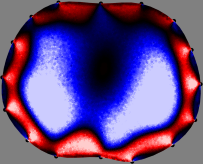

Figs. 3 and 4 compare the performance of the proposed FER method in (20) with the standard regularized least-squares method ((19) when is the identity matrix). The regularization parameter of the standard method was heuristically chosen for its best performance, and the parameter of the FER method was set to be one of three different values . The injection current was 1 mA at 100 kHz, and the frame rate was 9 frames per second. The reference frame at was obtained from the maximum expiration state. The measured data, , represent the voltage differences between each time and . The blue regions, which denote where conductivity decreased by inhaled air, increased during inspiration and decreased during expiration. The FER method with was clearly more robust than the standard method that produced more artifacts originated from the inversion process.

| Standard | |

||||||||||

| FER () | |

| FER () | |||||||||||